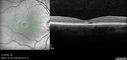

Dome Shaped Macula Left Eye153 views73 year old female Diagnosed with POHS in the past and treated with laser in the right eye in 1994 with vision loss. She moved from Tampa to Largo in 2017 and started seeing Dr. Cohen. She had her last injection in the left eye 2015 prior to moving to Largo. She has been treated intermittently in the left eye and has been resistant to Anti-VEGF injections. Her vision is good in the left eye. Images are from April 2023 one month following a Vabysmo injection in the left eye.

PMHx- thyroid disease

Meds: Synthroid

VA 20/200 OD, 20/25 OS